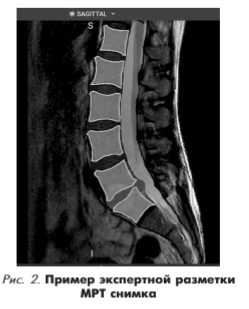

В результате экспертной разметки данных для обучения нейросети были подготовлены и размечены МРТ-снимки в сагиттальной плоскости, на которых были выделены разными цветами позвонки, межпозвоночные диски, грыжи с резорбцией, а также мышцы. Пример разметки приведен на рис. 2.